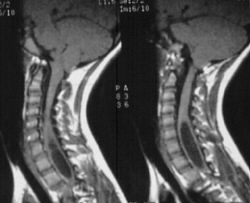

Refer to this picture for question 3.

3. The above condition can be caused by:

Refer to the picture above for question 4.

4. Recognized causes for the above condition include:

Refer to the picture above for question 5.

5. Causes of the above appearance include: